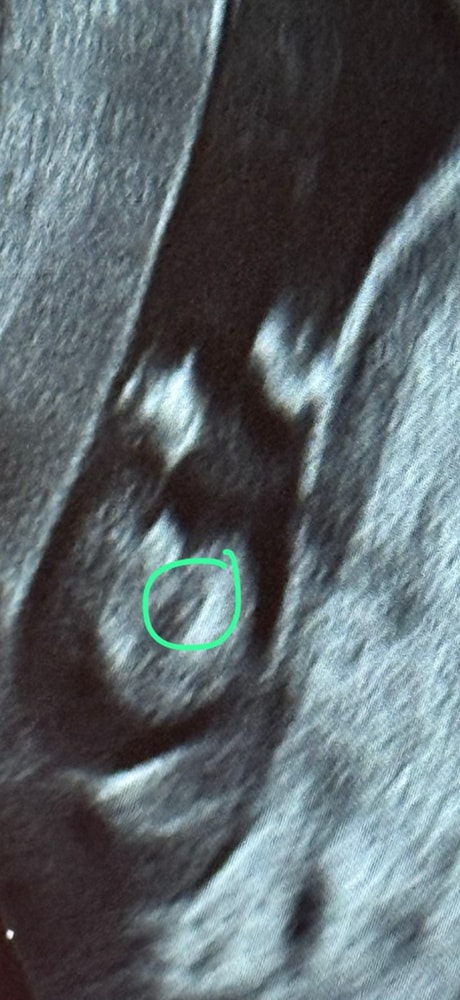

Маша, ну у вас по-моему это не пуповина, с первым сыном у нас писюн такой же был на экране, а в эту беременность вот так и то что я обвела зеленым меня смущает ибо узистка утверждала, что то, что обведено красным это писюн, но по-моему это как раз пуповина в срезе😅 Изображение Изображение Изображение

09.11.2025

Евгения, да уж ))) а у вас какой срок?

Маша, сейчас 17,5 а фото в 16 недель😁